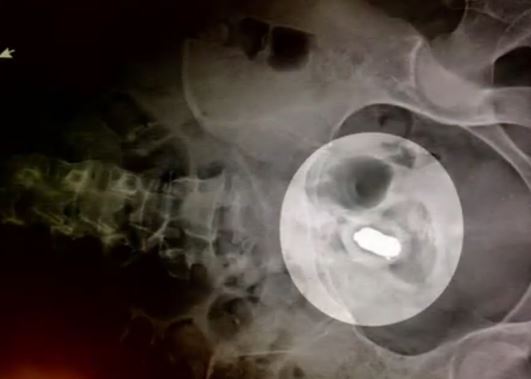

外科醫師喬治 (George Crawford) 見狀也傻眼了,他無法想像布列塔妮到底是做了什麼竟然玩具卡進了直.腸,甚至接近結.腸附近,「直腸的作用是讓便便不會掉出,如果你把東西放得夠上面,直腸就會把它吸進去」。好在布列塔妮的玩具沒有刺破腸壁,也沒有流血,最後喬治醫生用了金屬鉗將玩具順利取出。